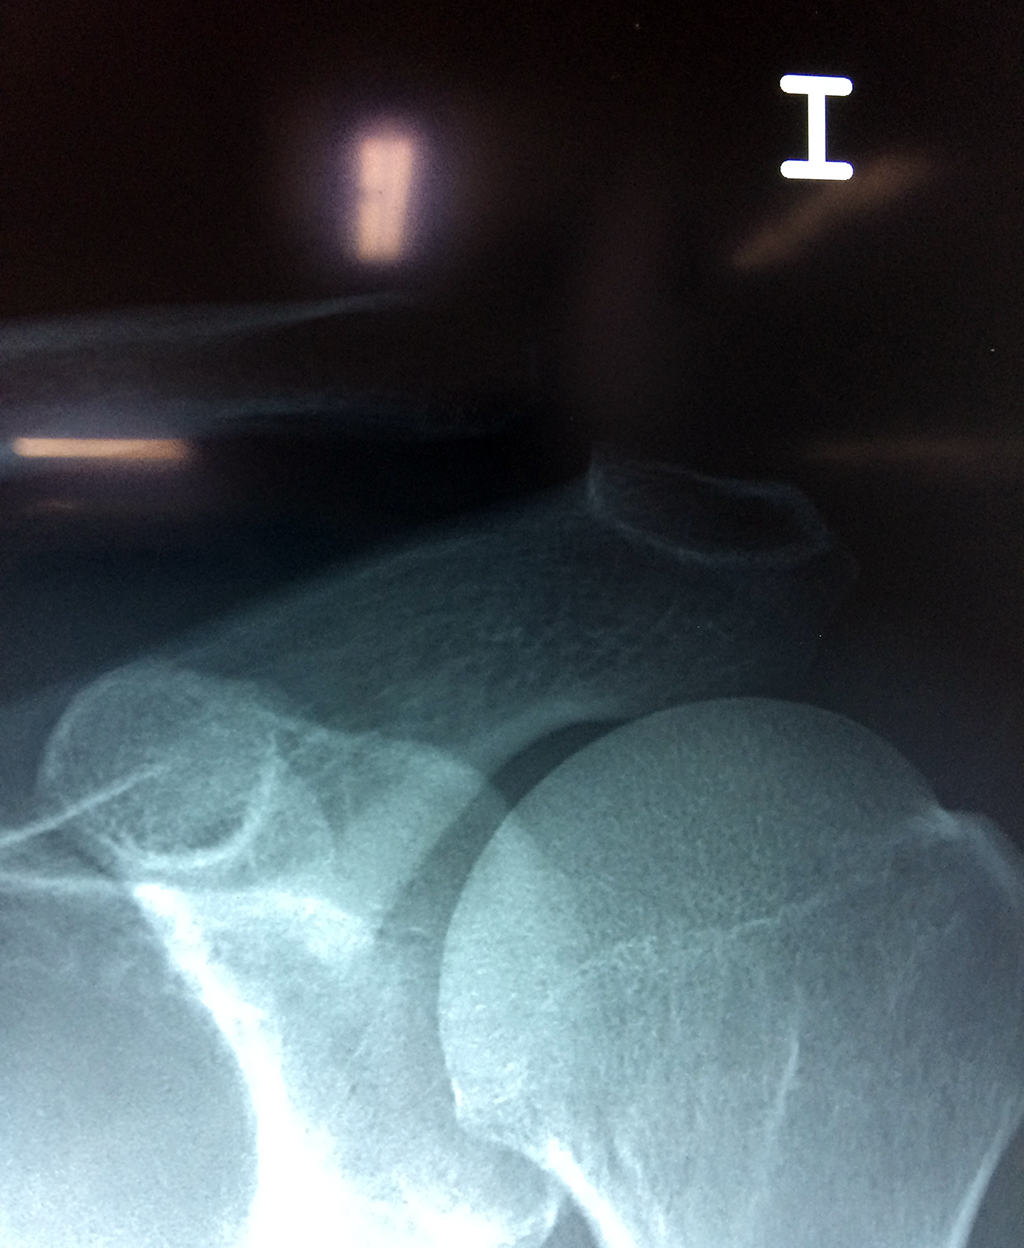

La clavícula es un hueso largo, con forma de "S" itálica, situado en la parte anterosuperior del tórax. Junto con la escápula forman la cintura escapular. Se puede palpar por toda su longitud y se extiende del esternón al acromion de la escápula, siguiendo una dirección oblicua lateral y posterior.

Se considera el único medio de unión entre el miembro superior y el tórax. A pesar de su aspecto, similar al de un hueso largo, posee una estructura semejante a la de un hueso plano, ya que carece de epífisis y de diáfisis, lo que la harían entrar dentro de la clasificación de hueso largo. Carece de un canal medular propiamente dicho.